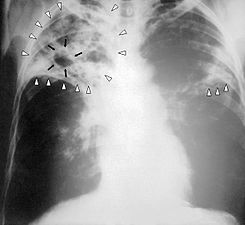

Question 31

Question

patologia que se observa en la siguiente imagen.

Answer

• asma

• tuberculosis

• enfisema